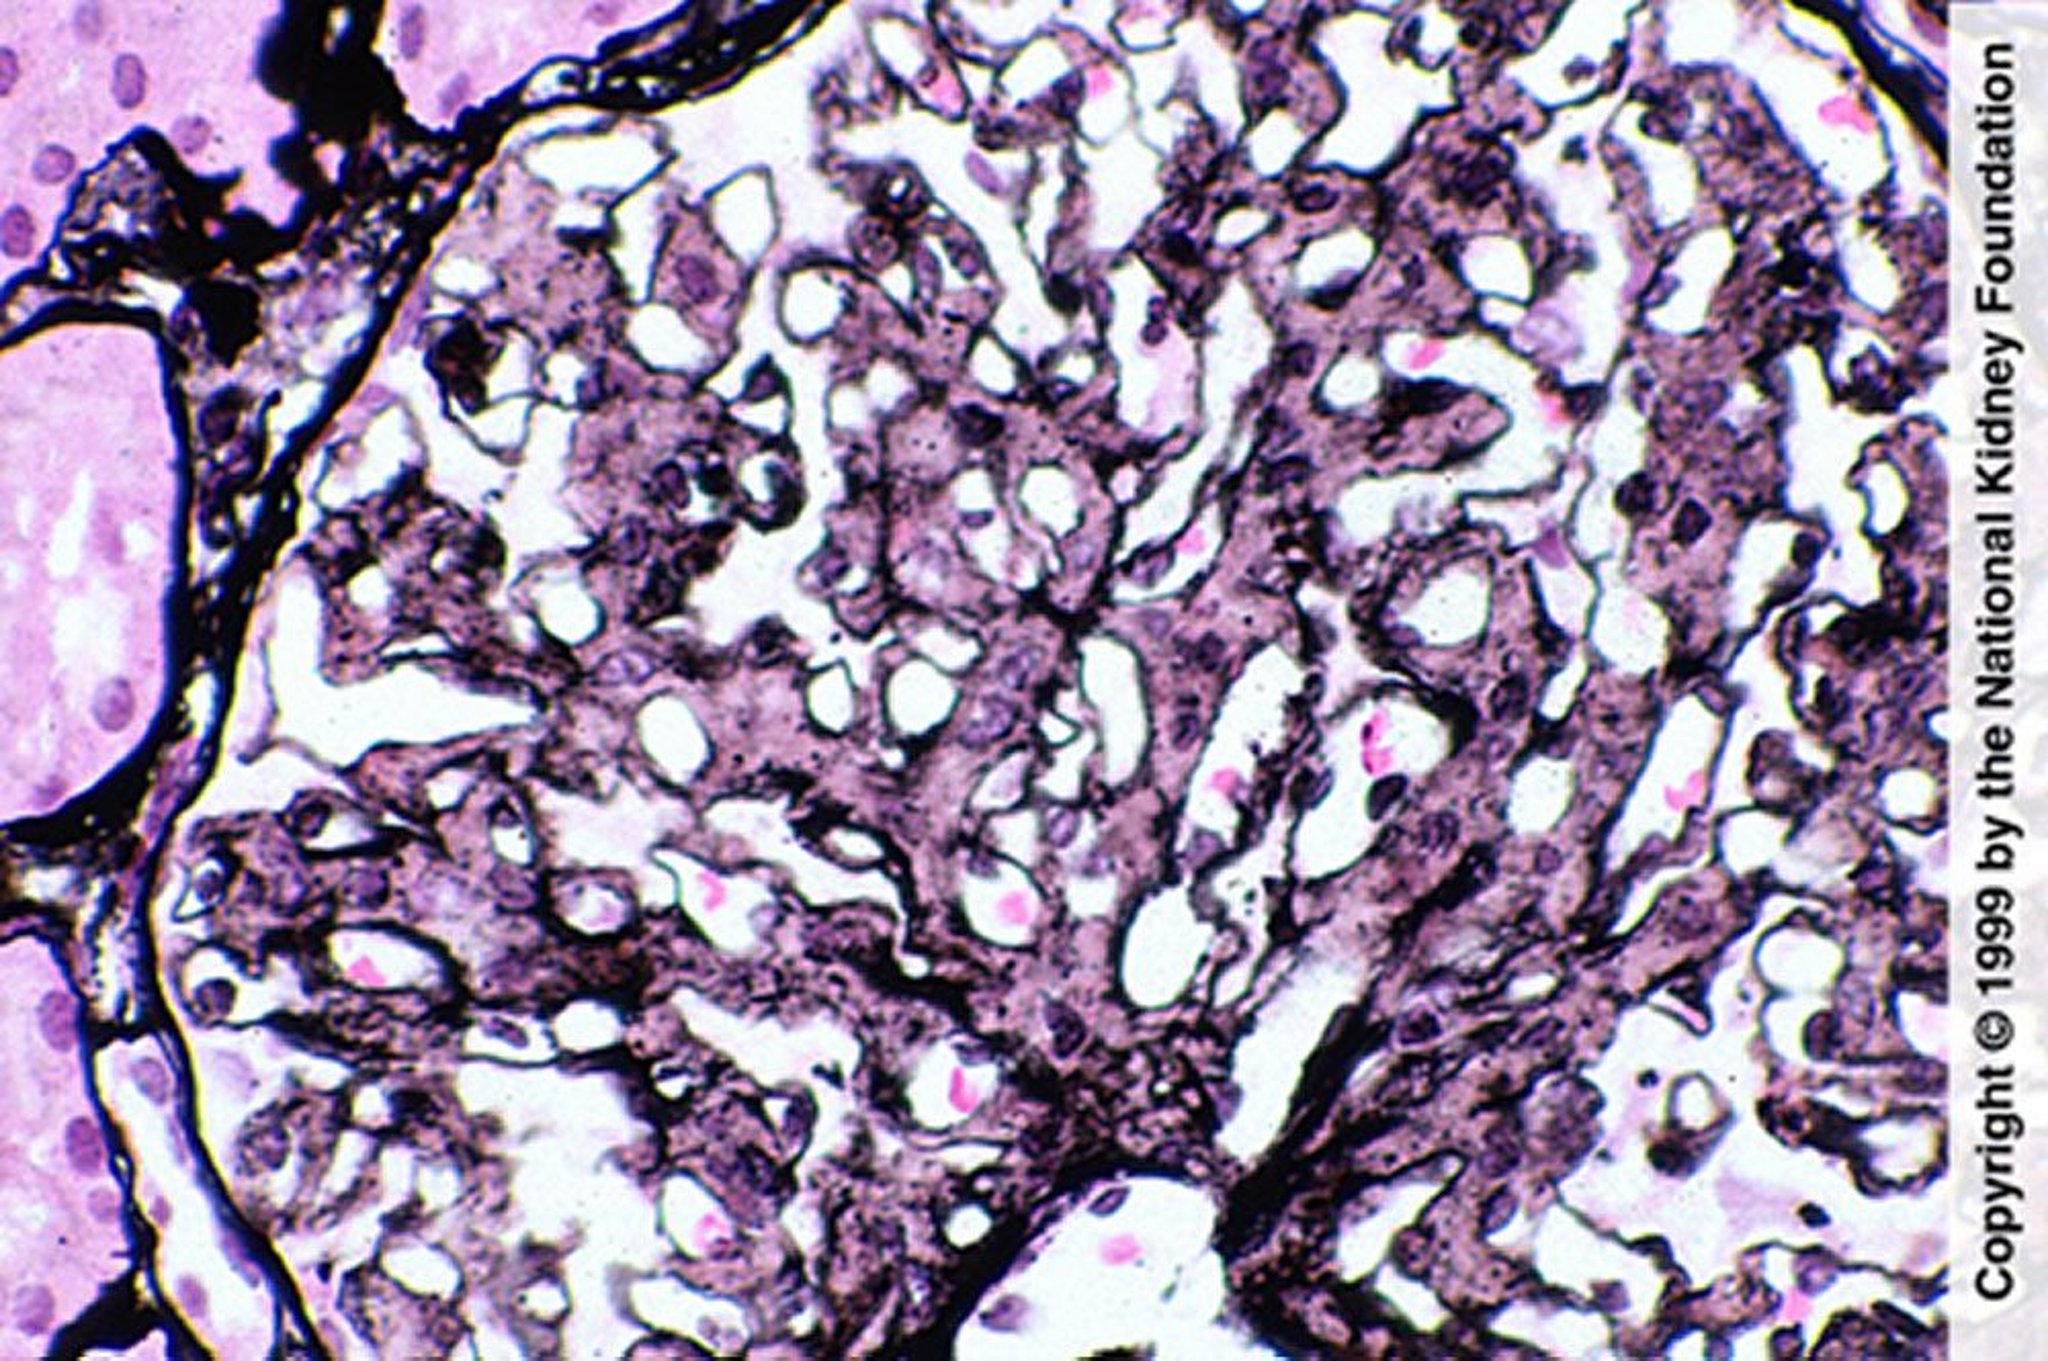

Glomerulopatia fibrillare (proliferazione mesangiale)

La proliferazione mesangiale è indicativa di glomerulopatia fibrillare; tuttavia, la diagnosi richiede una colorazione rosso Congo negativa, colorazione delle IgG mediante immunofluorescenza e dimostrazione delle fibrille alla microscopia elettronica (colorazione all'argento di Jones, ×400).

Imagine fornita da Agnes Fogo, MD, and the American Journal of Kidney Diseases' Atlas of Renal Pathology (vedi www.ajkd.org).